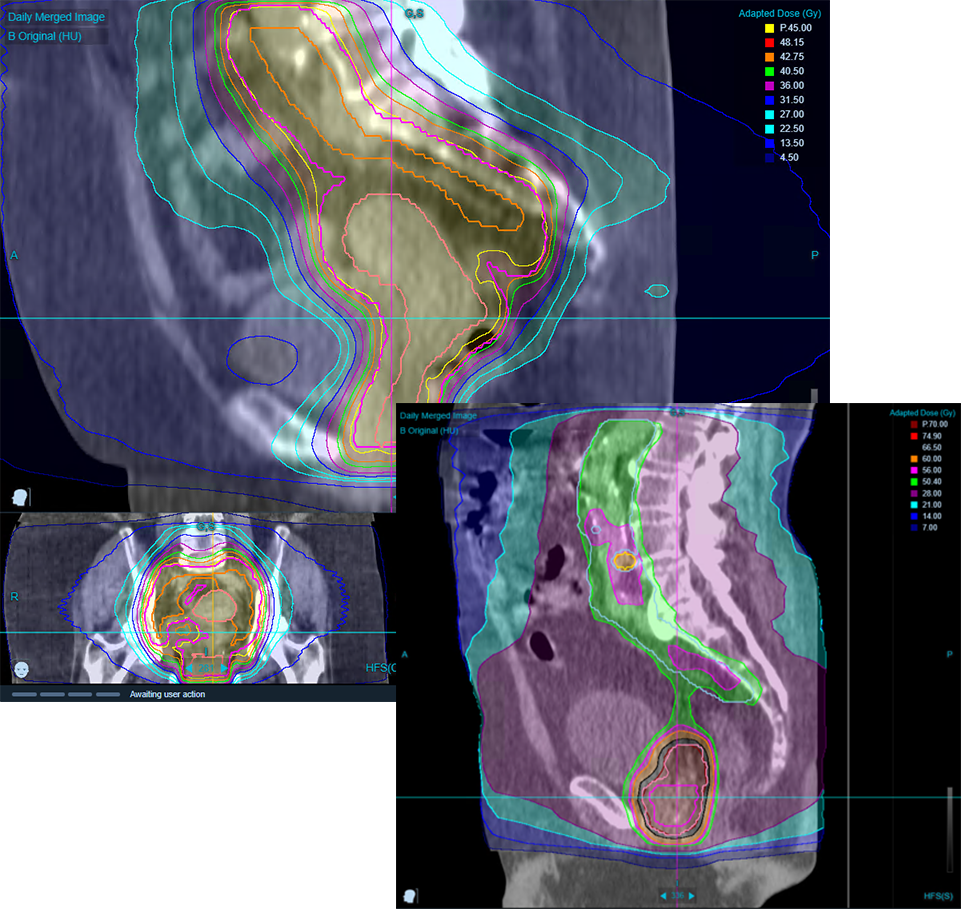

Highly Automated for Offline Adaptive

Time remains the most significant barrier to adopting and using ART in more practices and with more patients. Clinical workflows — plan adaptation in particular — are time – and labor-intensive. Accuray-proven PreciseART® software uses advanced automation to streamline and accelerate clinical ART workflows. Automatically monitor protocol-specific action levels, flagging cases for review and possible plan adaptation. Accelerate plan adaptation with contouring adjustments, maintaining the integrity of original treatment plan objectives to ensure tumor coverage, helping minimize dose to organ at risk (OAR) doses and reduce toxicity. Fully integrated offline systems to map daily high-fidelity ClearRT® helical kVCT images to the planning CT make it easier to assess dose distribution variations during the treatment course.  All without placing a heavy burden on clinical teams.